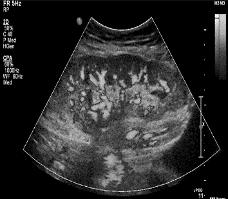

For testing, grayscale and color photos are obtained. The simulations are run on MATLAB R2021b with a Windows 10 operating system and 8 GB of memory. The test images are shown in Figure 6(a) to Figure 6(f). As a result, these cipher images provide no relevant information about the plain image. The plain images retrieve as it is after the decryption process. As we can see, our scheme can be implemented quickly. Table 1 shows the results of evaluation metrics between input and cipher image and time of encryption. Table 2 shows the results of evaluation metrics between the input image and retrieved image and the time of decryption. The tables display the results of the encryption and decryption of each image using three chaotic maps, to compare these results later and to determine the best map in the case of encryption and decryption.

(a) (b) (c) (d) (e) (f) Figure 6. Plain grayscale images with different sizes: (a) 512×512, (b) 600×600, (c) 900×900, (d) 1024×1024, (e) 612×612, and (f) 500×500